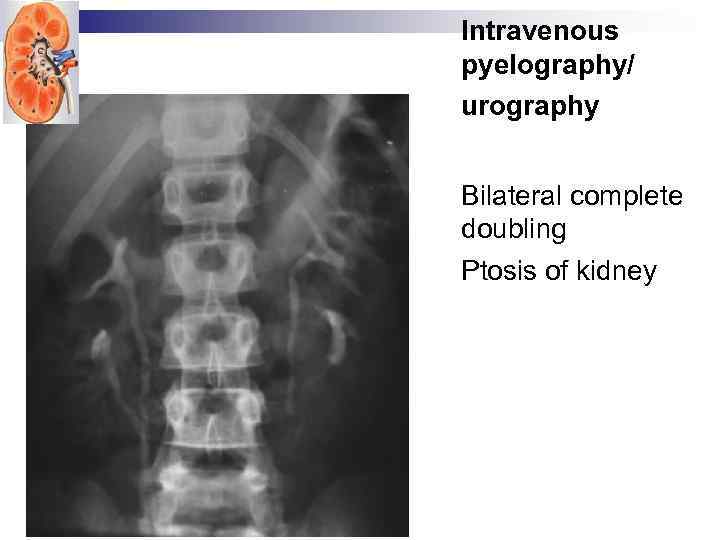

Intravenous pyelography/urography

Intravenous pyelography/urography

Intravenous pyelography/ urography Bilateral complete doubling Ptosis of kidney

Intravenous pyelography/ urography Bilateral complete doubling Ptosis of kidney